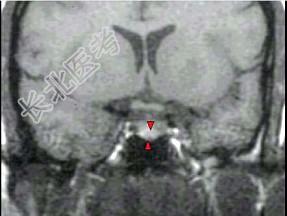

- 单项选择题女,38岁, 头痛、闭经,MRI检查如图, 最可能的诊断是 ( )

D、垂体微腺瘤